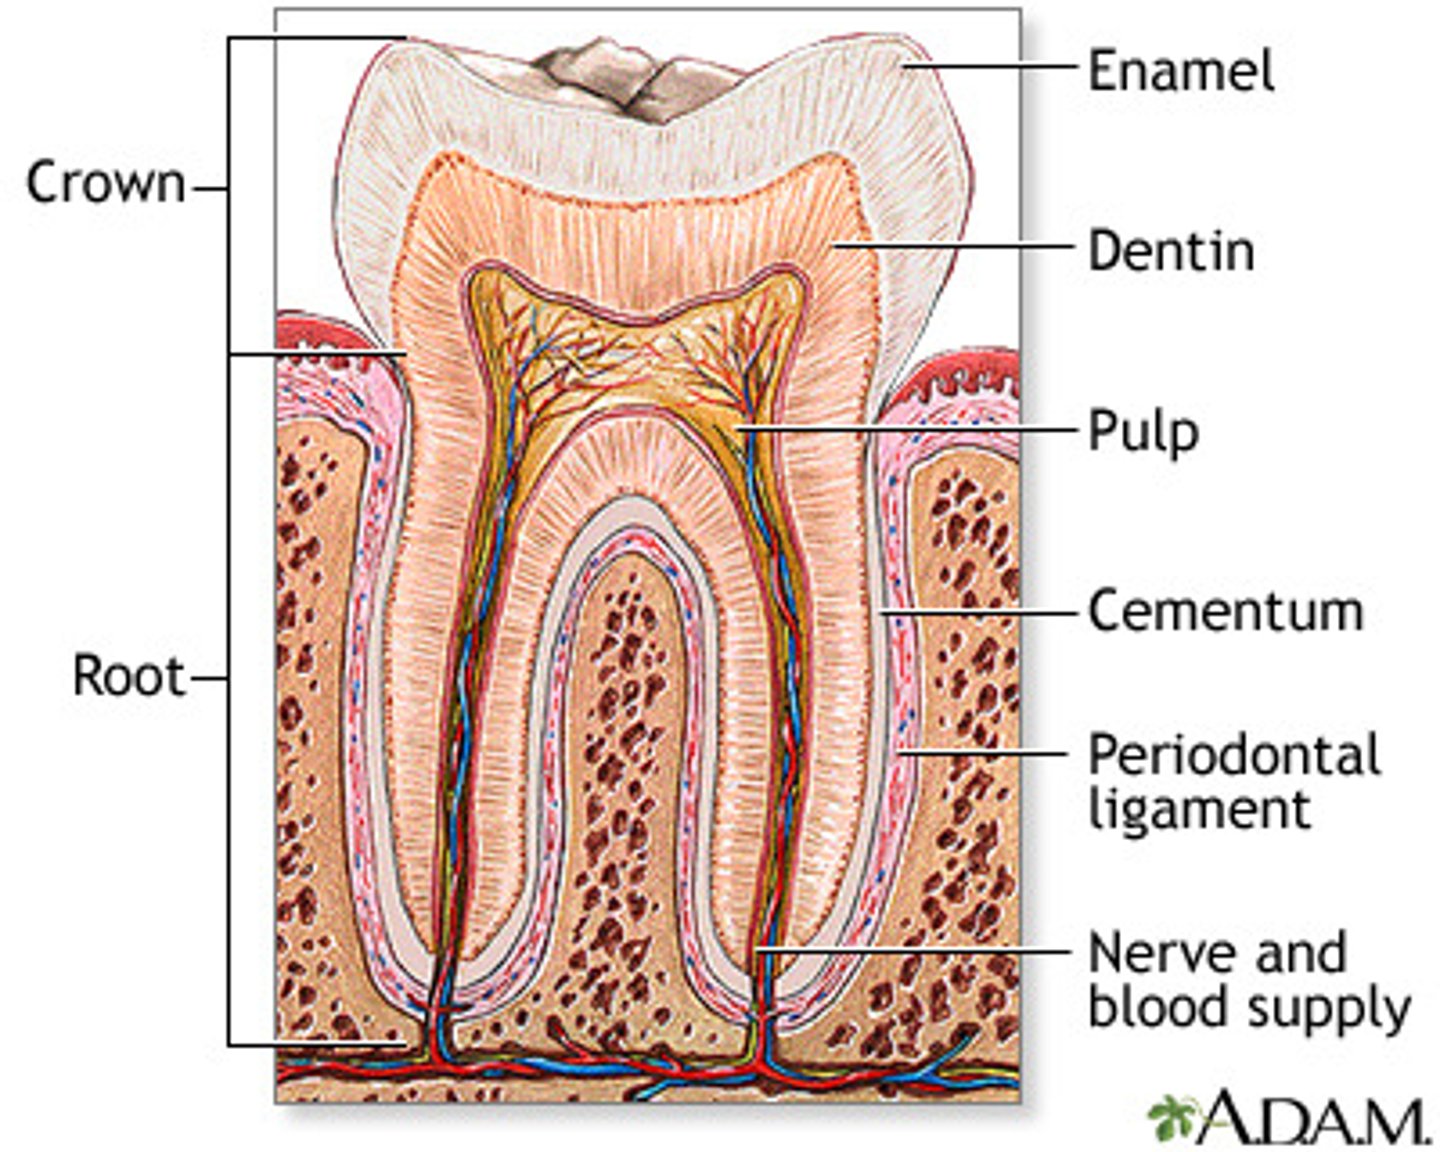

Tooth structure